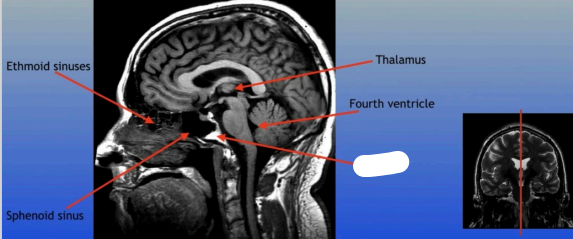

Thalamus

Ethmoid Sinuses

Sphenoid Sinus

Thalamus

Fourth Ventricle

Clivus